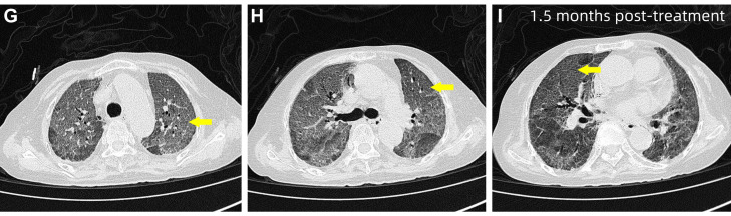

经过超过1个月的治疗后,患者呼吸困难较前改善,但未完全缓解。复查HRCT显示双肺弥漫性斑片状磨玻璃影伴小叶间隔增厚,呈“铺路石样”改变,并见局部空气支气管征。鉴于治疗改善不足,患者在行鼻导管吸氧(3L/min)的同时进一步行

图3 患者治疗1个多月后HRCT,显示双肺弥漫性斑片状磨玻璃影伴小叶间隔增厚,呈铺路石样改变(黄色箭头)